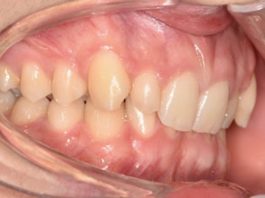

Malocclusione di classe II con morso profondo e lieve affollamento superiore anteriore trattata con...

La malocclusione di classe II può essere distinta in scheletrica e dentale. La malocclusione scheletrica di classe II si riferisce più spesso a una...

Trattamento ortodontico di un paziente in crescita con shift mandibolare anteriore: case report

La malocclusione di classe III presenta un’eziologia multifattoriale, nonostante ci sia una forte correlazione genetica nelle famiglie affette da tale malocclusione.

Quest’ultima può essere di...